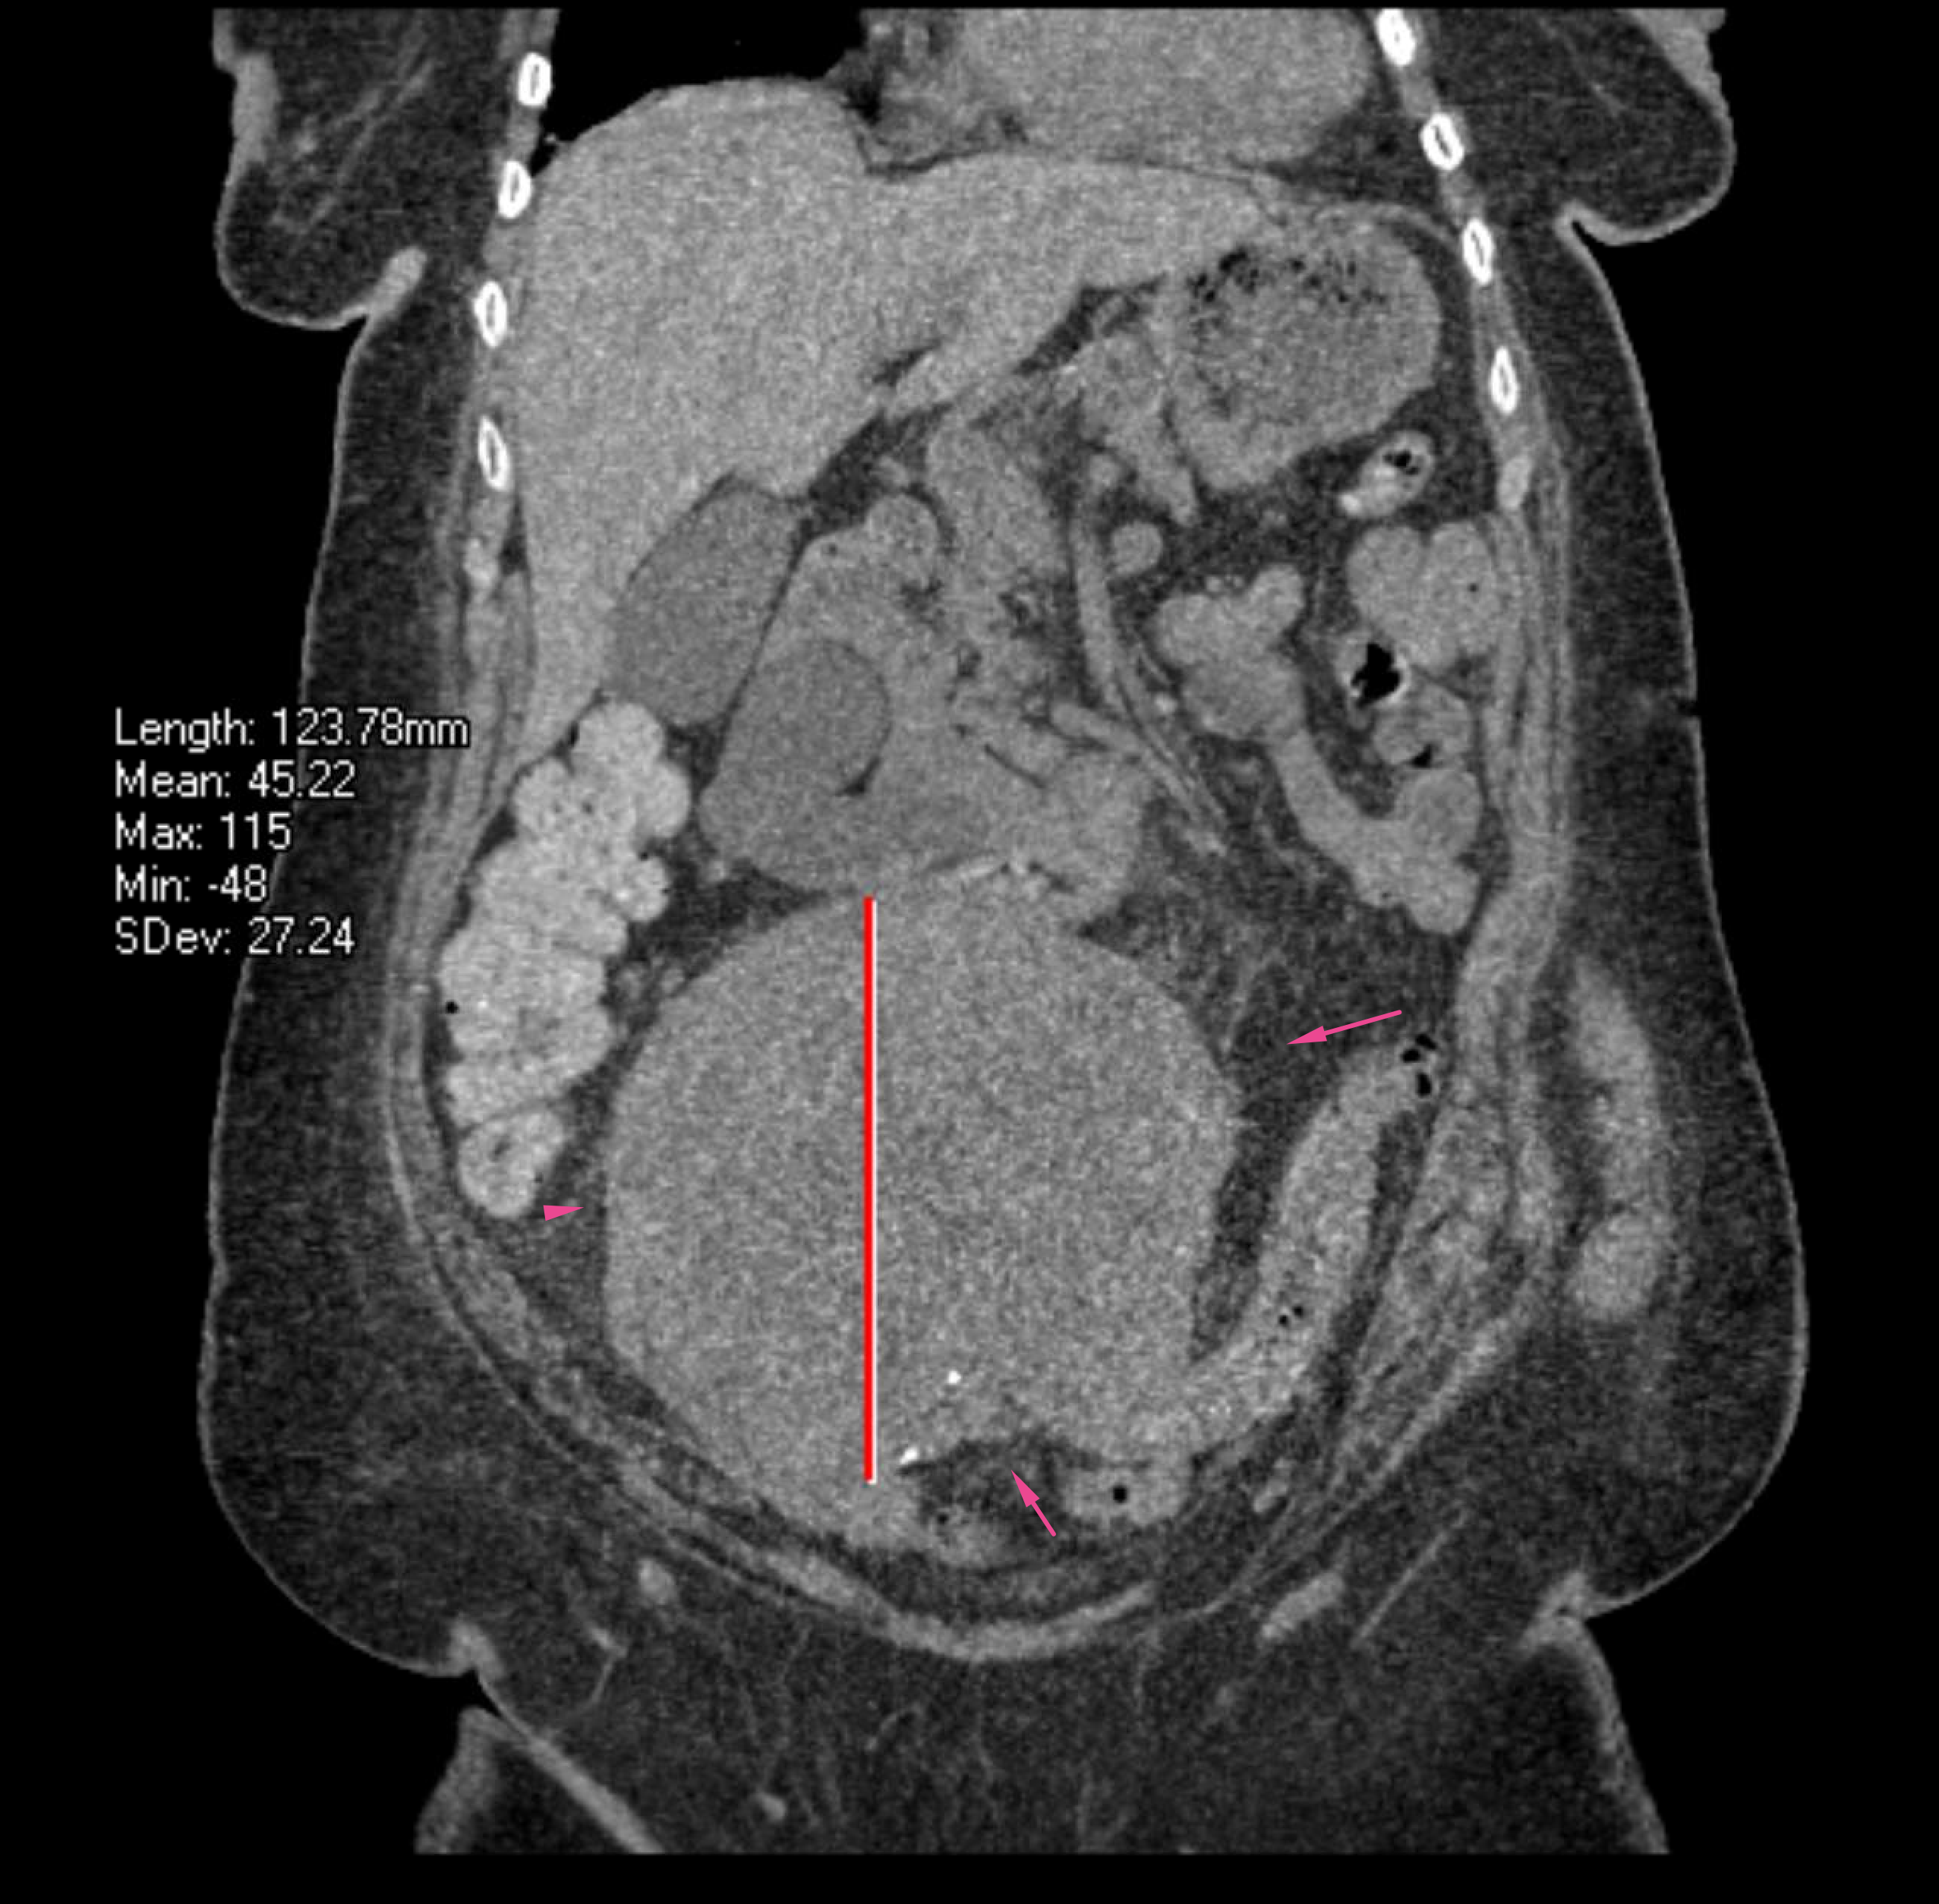

Age: 83

Sex: Female

Indication: GI bleed

Radiotracer: Tc99m labeled RBCs

Sample ReportNo evidence for active GI bleeding during the course of this study.

Hypervascular mass in the lower abdomen and pelvis. Recommend CT for further evaluation if not previously performed.